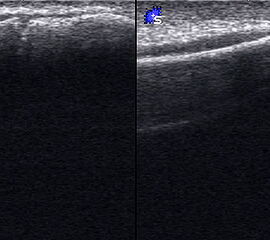

Fibulaverletzung beim Erwachsenen

Fibulafraktur mit Unterbrechung der Kortikalis und Hämatom.

Abbildung 13

Lagerung: Rückenlage, leichte Innrotation des Fußes.

Schnittebene: LS über distaler Fibula.

Referenzstruktur: Fibula im Längsverlauf.

Befunde: Bei einer Außenknöchelfraktur ist eine Unterbrechung der echogenen metaphysären Knochenlinie mit umgebendem flachen, echoarmen periostalen Hämatom zu sehen (Abb.13).

Cave: Ein Os subfibulare kann ebenfalls fälschlicherweise als Fibulaverletzung interpretiert werden!